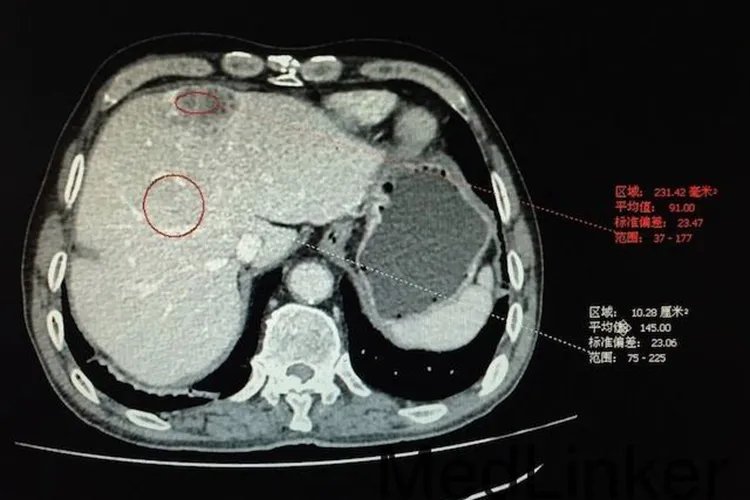

肿瘤CT图片

肝癌肝癌表现为肝内局限的或多发的结节状或较大的肿块,CT平扫为低或等密度,巨块型者常有中心更低密度区,少数边界清楚并有假性包膜形成,增强后的动脉期可见肿瘤的实质部分强化,中心为不强化的低密度坏死区,其强化效应在静脉期和平衡期消失,静脉期还可以见到门静脉的癌栓征象。